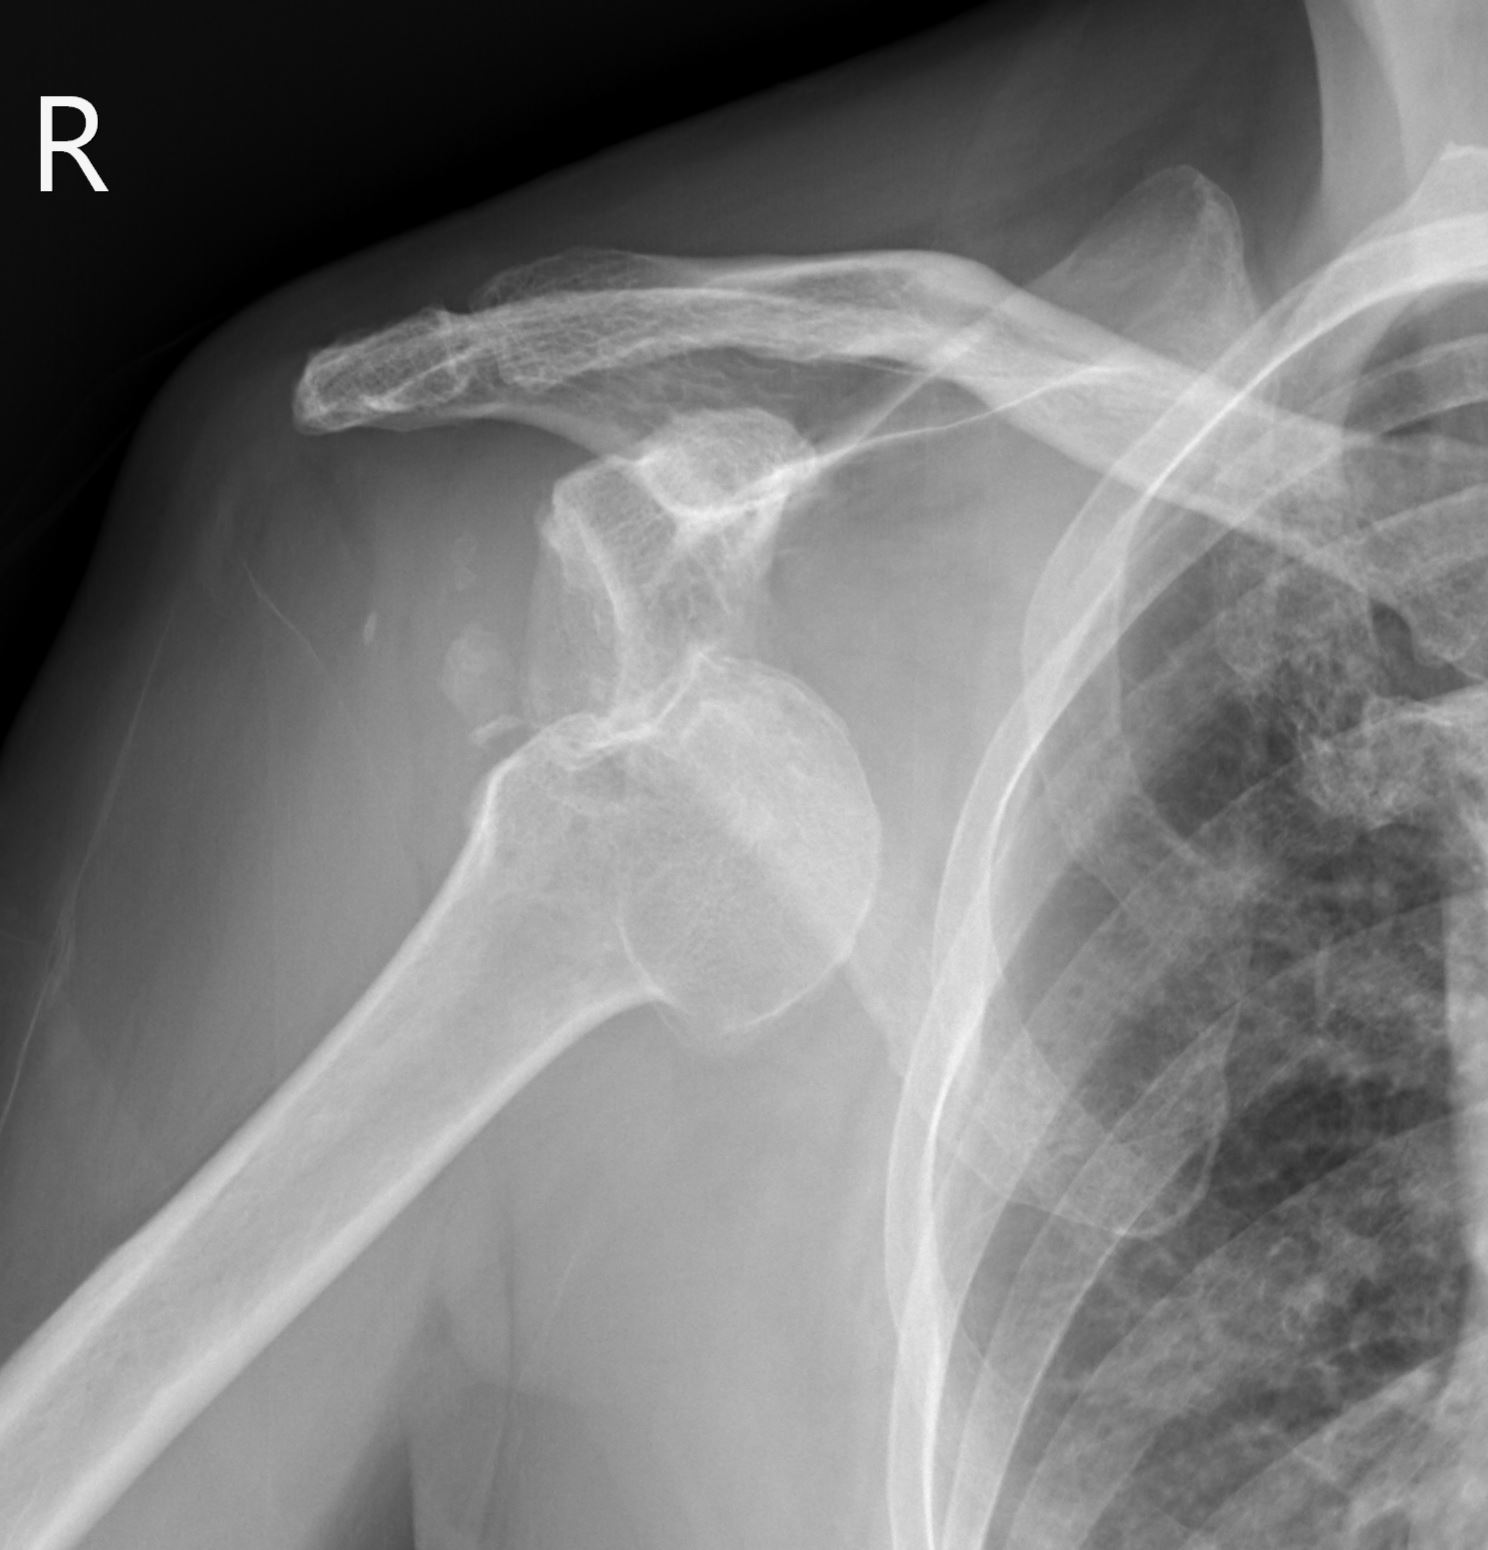

個案70歲女性,跌倒撐地後右肩疼痛無法動,圖片1的X光可見右肩關節前脫位。我們先執行鎖骨上臂神經叢阻斷術(影片1),然後由肩棘部下方進行橫向掃描,記錄前脫位復位前的影像 (圖片2、影片2),在患者疼痛大幅減少後進行徒手復位,復位後會立即執行超音波的確認(圖片3、影片3),最後三角巾固定後追蹤復位後的X光(圖片4)。

圖片170歲女性右肩關節前脫位肩部X光